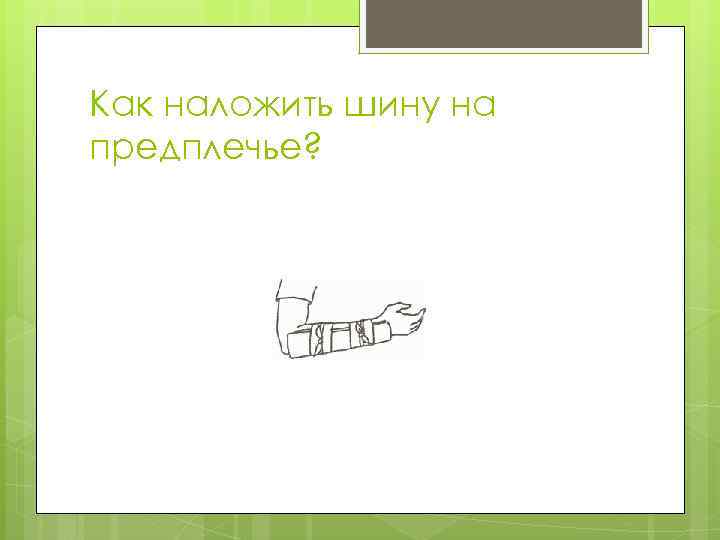

Как наложить шину на предплечье?

Как наложить шину на предплечье?